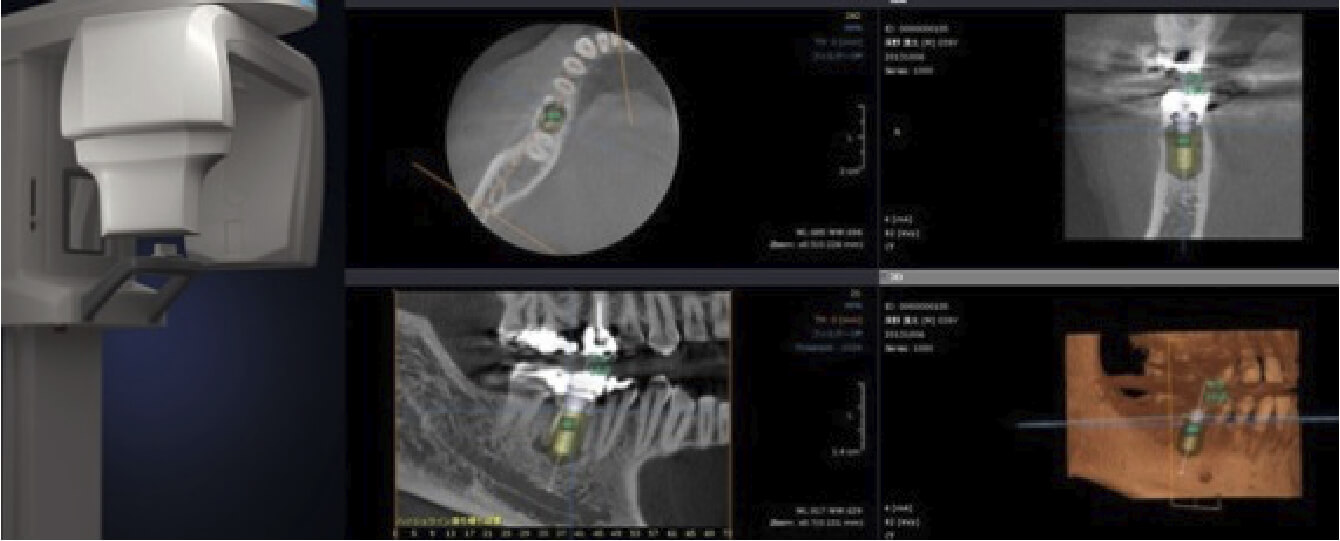

診査には、一般診査(問診、視診、パノラマエックス線検査、歯周病検査)および、模型診査、CT撮影、を行っております。

※画像はストローマン社の許可を頂いております。

当院では完全個室の診療室を設け、インプラント治療に必要な最新のCT撮影機を完備しております。インプラント治療はもちろん、口腔外科や歯内療法、歯周病治療などの分野で活躍します。このCT撮影機では歯や骨、神経、血管等を三次元的に診る事が出来、正確な距離も測ることが出来、診断や術後の経過を観ていくために、大変役に立ちます。また、コンピューター上でシュミレーションできるため、来院回数や時間の短縮につながります。デジタル化することにより被ばく量も最小限に抑えられ全に治療を受けていただけます。